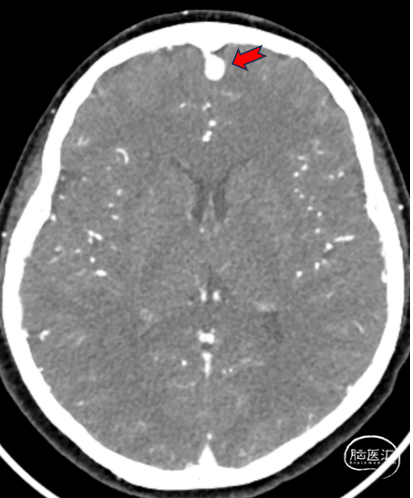

MRA:红色箭头所指异常血管影,DAVF可能。

➢术前影像学检查:CTA及MRA提示左侧前颅底硬脑膜动静脉瘘(DAVF)。

➢初步诊断:左侧前颅底DAVF。